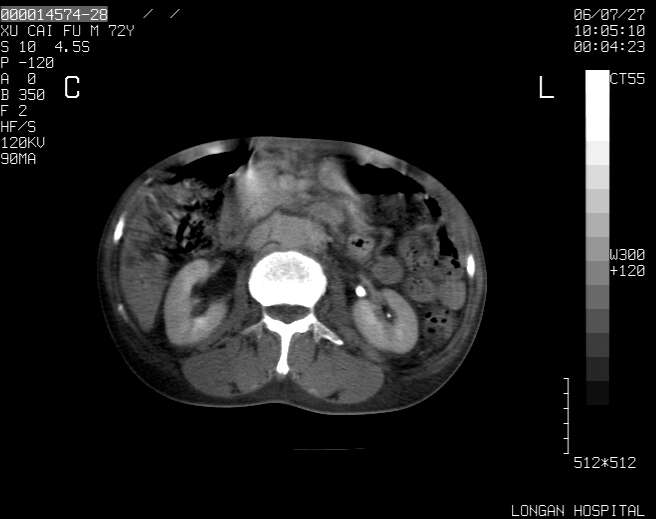

以下是引用winter在2006-7-30 20:14:00的发言:[br]1、考虑胆囊癌伴胆道侵犯并高位胆道梗阻、肝内多发转移、腹膜后淋巴结转移。[br]2、右肾轻度积水。[br]3、老人家72岁了胰腺头体尾部均较饱满,不过未见密度异常及其他异常征象。[br]4、腹水。

以下是引用jiajie在2006-7-31 7:10:00的发言:[br]考虑肝转移瘤,腹膜后淋巴结增大。[br]胃癌不能除外,建议胃镜检查。